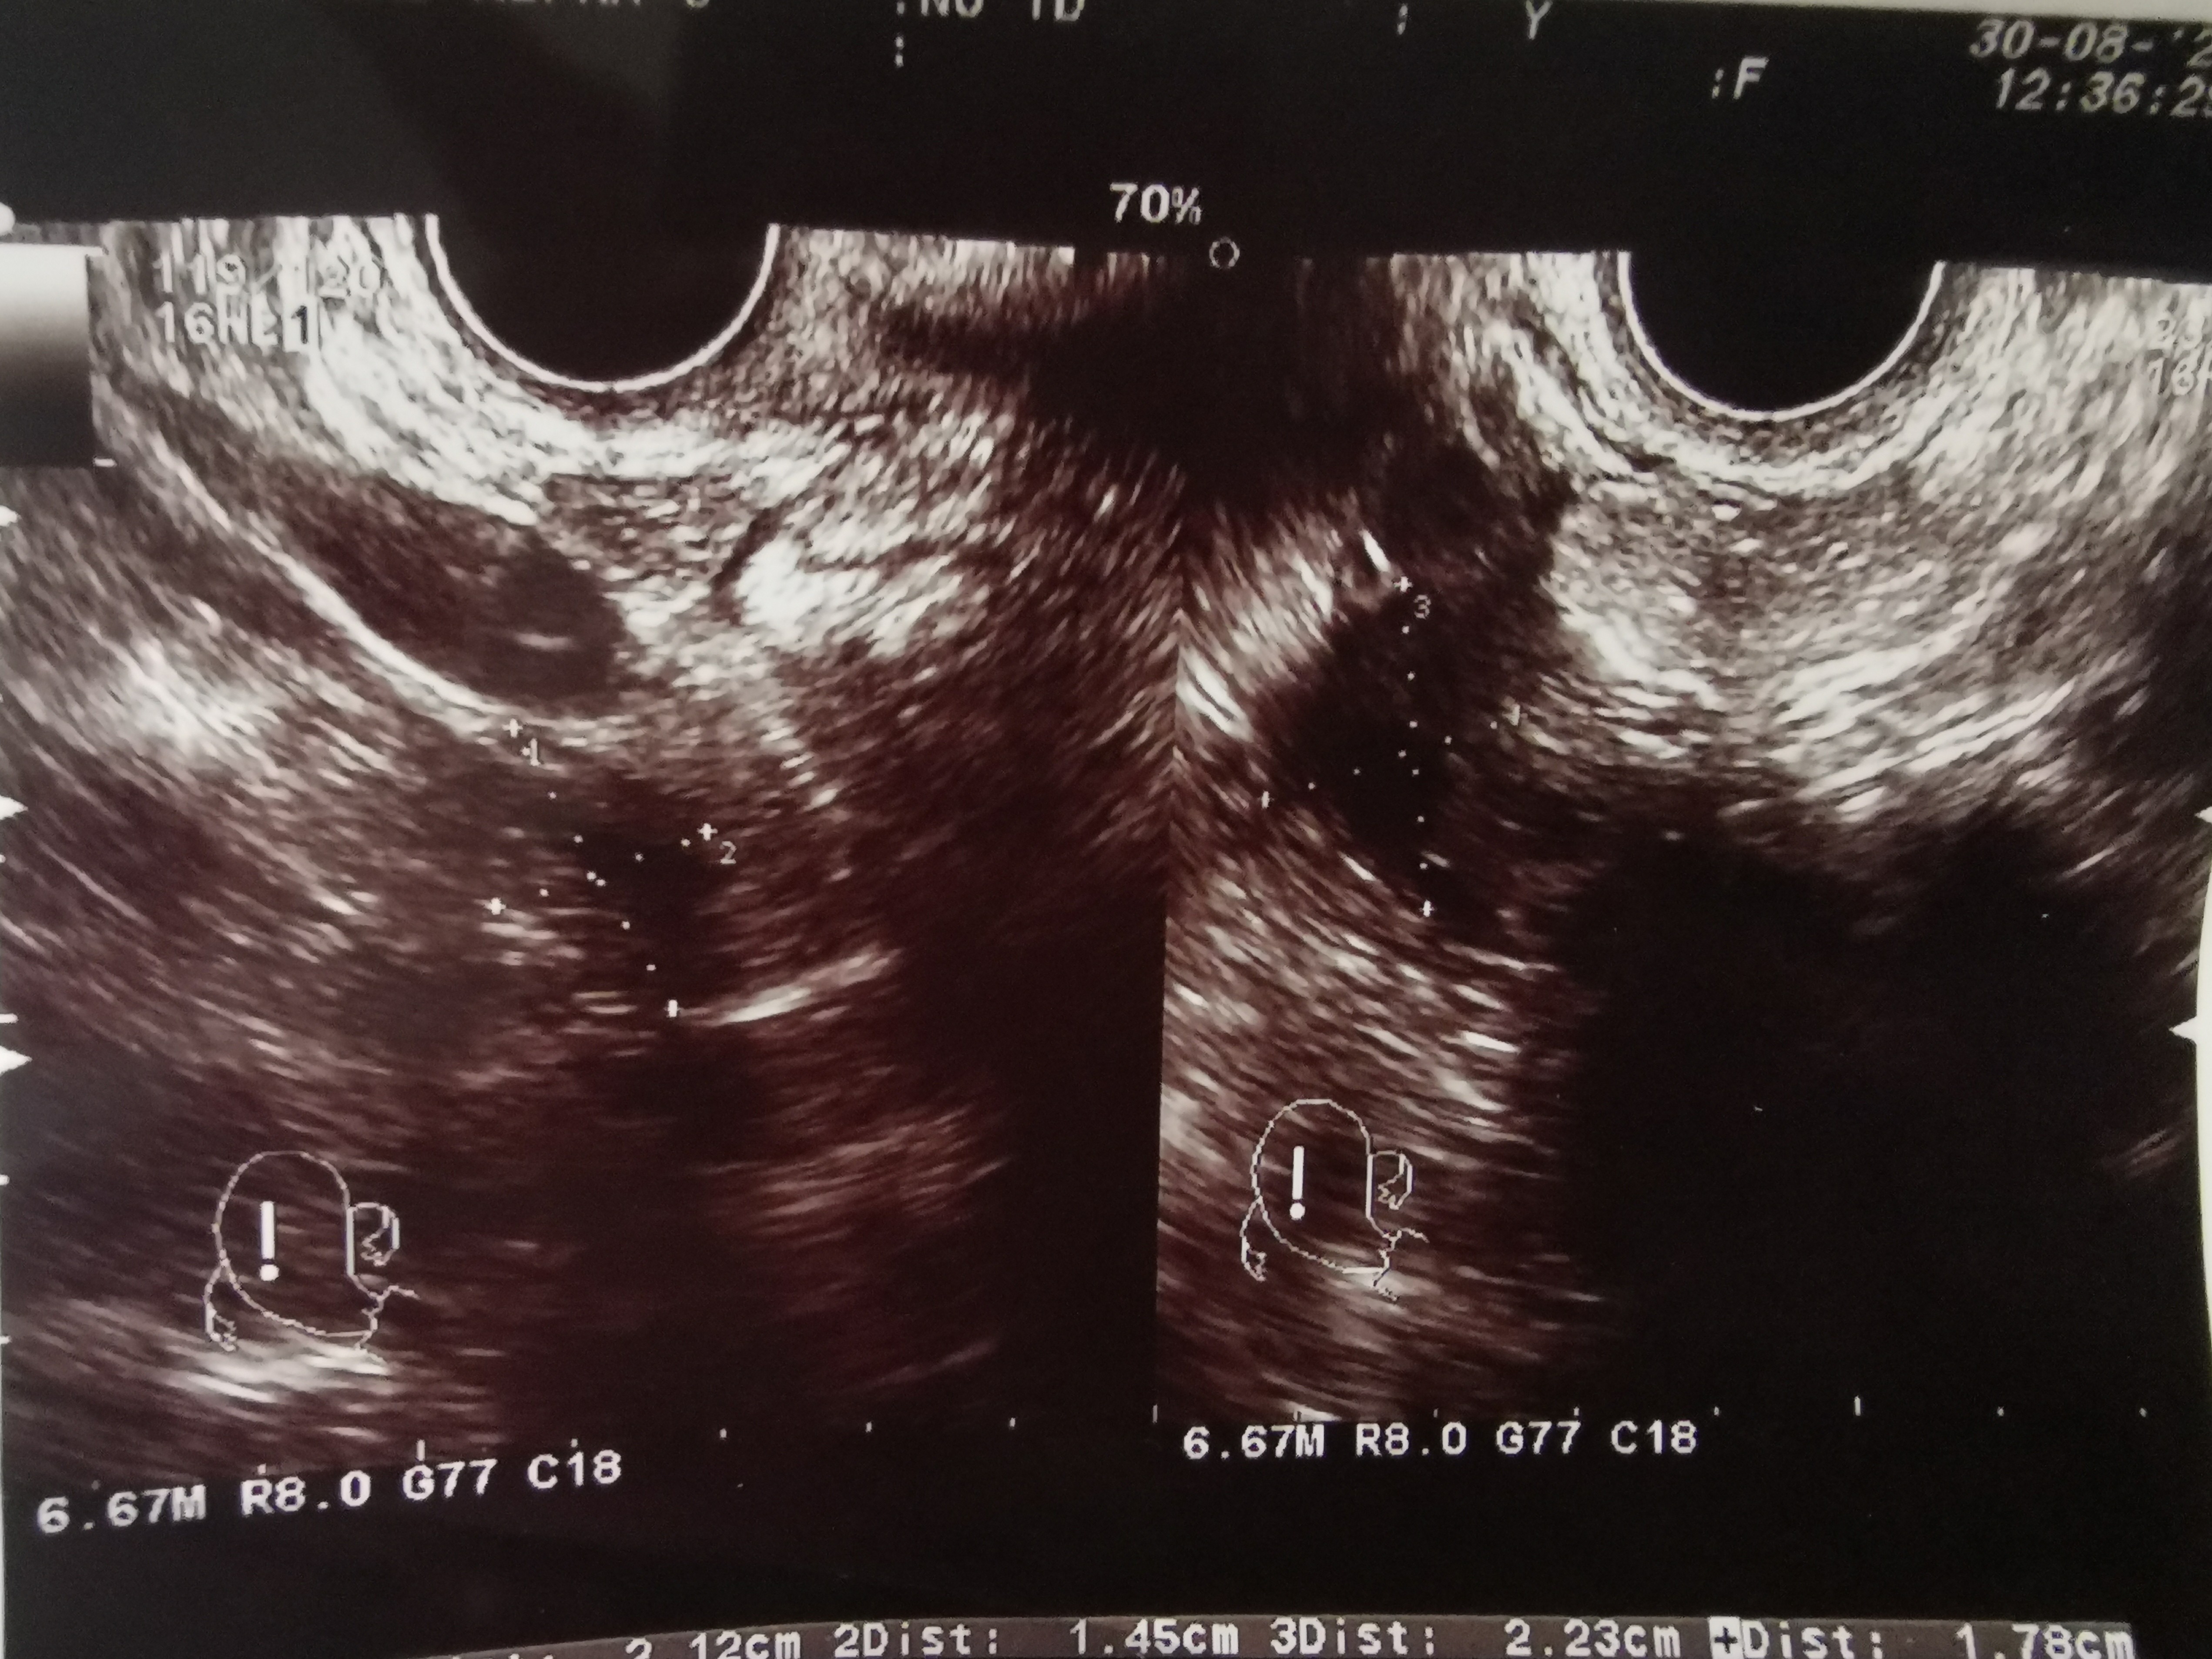

Ej bo teraz mnie to nurtuje. Lekarz nic nie mówił, a ja nie pytałam. Jak byłam na wczesnej ciazy, zrobił zdjecie zarodka, ale był tam pęcherzyk, tzw. Osobny. Kto to wyjaśni? Może miały być 2 ale coś poszło nie tak i lekarz dlatego nic nie wspominał, bo pewnie to się często zdarza. Nie, nie doszukuje się, po prostu mnie to nurtuje. Jak będę miala czas to wstawię zdj usg

Może to poprostu było jakieś zamazane i tak wyglądało.

Też raz tak miałam i się wszyscy śmiali, że bliźniaki.